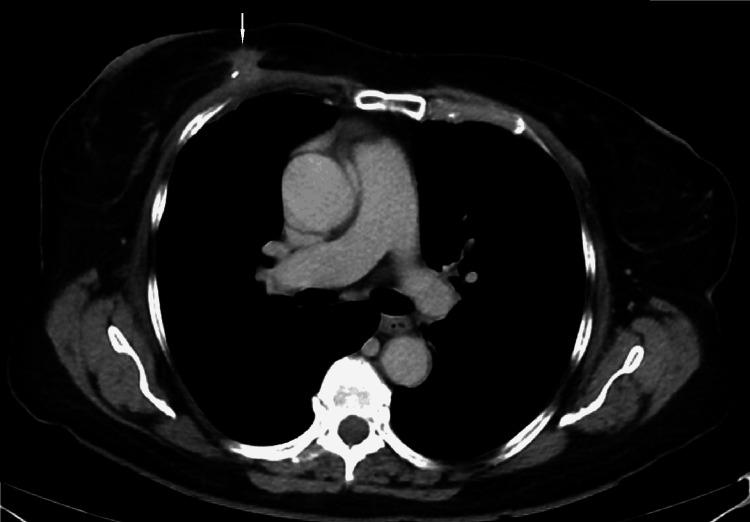

We describe a case of pathology-proven invasive lobular breast cancer (ILC) arising in a scar over 15 years after lumpectomy for previous invasive ductal carcinoma (IDC). The tumor was detected on screening mammography as a new focal asymmetry at the scar site and confirmed at diagnostic mammography. Ultrasound demonstrated an irregular, shadowing, hypoechoic mass at the scar site. Ultrasound-guided biopsy revealed poorly differentiated invasive lobular carcinoma. MRI and CT showed an irregular mass with pectoralis muscle invasion. Multimodality imaging findings are described. This is the first case to our knowledge reporting multimodality imaging findings of a breast cancer developing at the site of a surgical scar that is histologically different from the originally resected cancer.

我们描述了一例经病理证实的浸润性小叶乳腺癌(ILC)病例,该病例发生于先前因浸润性导管癌(IDC)行肿块切除术后15年以上的瘢痕处。肿瘤在筛查乳腺X线摄影中被检测为瘢痕部位新出现的局灶性不对称,并在诊断性乳腺X线摄影中得到证实。超声显示瘢痕部位有一个不规则、有阴影、低回声肿块。超声引导下活检显示为低分化浸润性小叶癌。MRI和CT显示有一个不规则肿块,侵犯胸大肌。描述了多模态成像结果。据我们所知,这是首例报告手术瘢痕部位发生的组织学上与最初切除的癌症不同的乳腺癌的多模态成像结果的病例。